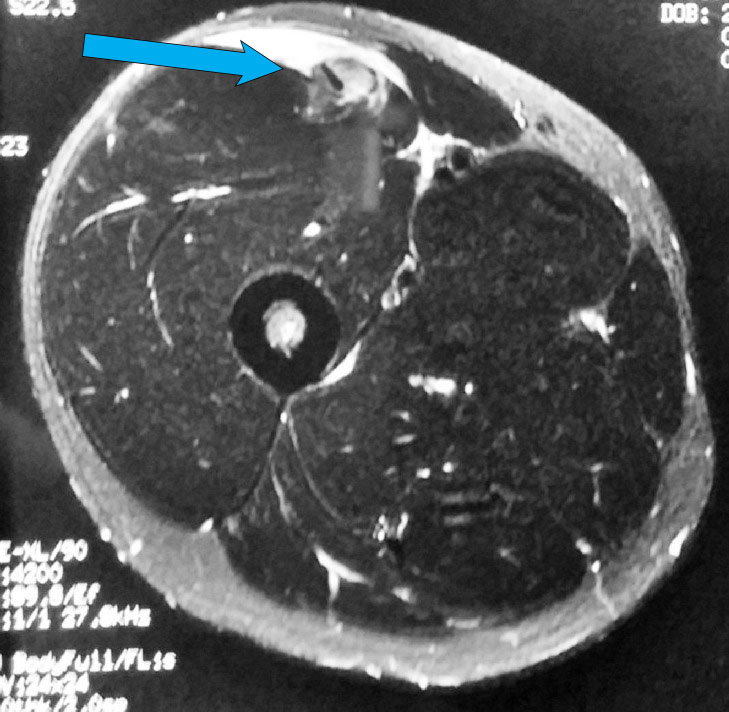

A young man experienced some minor right groin pain with sporting activities over the past 1 month. He continued to engage in sports despite the occasional right groin pain or discomfort.

He was playing football when he felt a muscle over the front of his right hip “tear”. He had sudden onset of right groin pain and was unable to continue running.

Examination showed tenderness over the front of his right hip and proximal right thigh with weakness in right hip flexion.

A clinical diagnosis of a possible right quadriceps muscle tear was made.

An MRI scan of his right thigh was ordered. The MRI confirmed a tear of the direct head of the right rectus femoris.

He was offered surgical repair of the torn rectus femoris.